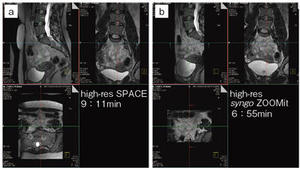

3Dイメージングの大きな問題点として,撮像時間の長いことと観察領域の拡大がある。syngo ZOOMitによる局所励起を用いることで,3Dの2方向の折り返しが回避できるため,オーバーサンプリング部分の撮像時間が短縮できる(図4)。また,折り返しを回避できることから,3Dイメージングにおける局所の面内分解能が向上する。加えて,FOV外からのモーションやフローアーチファクトを低減できるため,体幹部の呼吸,腸管の蠕動や頸部の嚥下による画質低下を回避することが可能である。あまり注目されていないが,実際に3Dイメージングクオリティを低下させる大きな要因の1つとして,大きなturbo factorがもたらす長いduration timeによるT2フィルタリング効果がある。syngo ZOOMitによりオーバーサンプリングレスが実現したため,これら3Dイメージングによる問題点が解消され,特に弊社3DイメージングシーケンスであるSPACE画像の画質向上により,低組織コントラスト分解能の向上による病変の検出,良悪性診断の向上が期待できる(図5)。

| 婦人科疾患における syngo SPACEを用いた3D画像(図4 a)。isotropicデータにより病変の広がり診断に期待が大きい。しかし,3Dシーケンスであるため,腸管や呼吸による体動の影響を受けやすく,また目的以外の信号の折り返しを低減するために各方向にオーバーサンプリングが必要であり,低組織間コントラスト分解能を維持するためには撮像時間の延長が懸念される。一方,局所選択励起を3D画像に適応することで,撮像時間の短縮,目的領域以外の信号源の混入を防ぐことができ,高い組織コントラストを短時間で提供できる(図4 b,5)。 | |